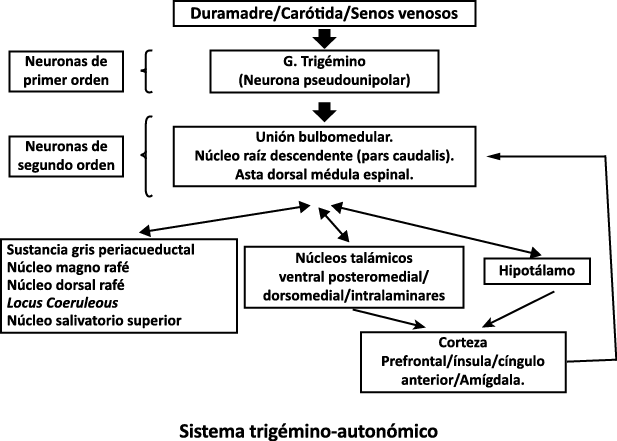

Todo lo mencionado contribuye al fenotipo del migrañoso y son vías que continuamente se están explorando para el desarrollo de nuevas terapias agudas y preventivas del dolor, más seguras y eficaces. Sin embargo, existe una controversia que gira en torno a dos cuestiones: la iniciación y el origen del dolor además de que todavía no se conoce el origen de los mecanismos neuronales que subyacen a la condición primaria en las personas susceptibles. Definitivamente la migraña implica la activación y sensibilización de las vías trigeminovasculares, así como el tronco cerebral y los núcleos diencefálicos(88). La vía aferente comienza en las aferentes vasculares nociceptivas de la duramadre que están para advertir, no para localizar. Su proyección al tálamo y la corteza y como se regula esta vía en cada nivel y por múltiples sistemas, ofrece la posibilidad de comprender los síntomas complejos y orientar las terapias. Los ataques comienzan como síntomas premonitorios, dificultad para concentrarse, bostezos, fluctuaciones del humor; y cambios homeostáticos, como la alimentación y el equilibrio de líquidos, que pueden incluir sensibilidades más generalizadas, como fotofobia y fonofobia. La fase premonitoria da paso a la fase de dolor con el sufrimiento acompañante y termina en una fase posdrómica de sentirse agotado por la experiencia. (Figura 1)

Un principio importante de esta teoría es que el desencadenante principal de la migraña proviene de la periferia, en los vasos sanguíneos de la duramadre, con la activación del sistema trigeminovascular proveniente del disparo de las neuronas trigeminales periféricas de primer orden en respuesta a una lesión nociceptiva o señales provenientes de las meninges que liberan mediadores neuroinflamatorios. La activación sostenida de las neuronas nociceptivas meníngeas durales provoca la activación secuencial y la sensibilización de las neuronas trigeminovasculares de primer orden (nociceptores periféricos), segundo orden (a nivel del TCC-complejo trigémino cervical) y tercer orden (trigeminotalámico), (Figura 5) así como la activación ascendente del cerebro, tallo y otras estructuras diencefálicas(97).

El dolor de cabeza asociado con un ataque de migraña, puede incluir la región frontal, temporal, parietal, occipital y cervical alta, es consecuencia de la activación del sistema trigeminovascular. (Figura 10)

La anatomía del sistema trigéminovascular ha sido bien descrita durante los últimos 70 años y esto ha ayudado a comprender la fisiopatología de la migraña y la distribución de su dolor. Se sabe que el cerebro es en gran parte insensible, pero un rico plexo de fibras nerviosas nociceptivas que se originan en el ganglio del trigémino inervan los vasos sanguí- neos de la piamadre, la aracnoides y la duramadre, incluidos el seno sagital superior y la arteria meníngea media, así como las grandes arterias cerebrales. (Figura 11) (23)

La inervación nociceptiva de la vasculatura intracraneal y las meninges incluye proyecciones axonales no mielinizadas (fibras C) y mielinizadas delgadas (fibras Aδ), principalmente a través de la división oftálmica (V1) del nervio trigémino, pero también, en menor medida, a través del nervio maxilar. (V2) y divisiones mandibulares (V3). También hay inervación neuronal de la duramadre desde los ganglios de la raíz dorsal cervical (24) (Figura 12).

Los terminales axónicos de las fibras nerviosas nociceptivas que inervan la duramadre contienen neuropéptidos vasoactivos CGRP, sustancia P, neurocinina A y péptido activador de la adenilato ciclasa pituitaria (PACAP)(25) (Figuras 13 y 14), que se cree que son liberados tras la estimulación que causa la vasodilatación de los vasos durales y piales(26) (Figura 15).

Hay una proyección aferente central desde el ganglio del trigémino que ingresa a la médula caudal del tronco encefálico, a través del tracto del trigémino, que termina en el núcleo espinal del trigémino caudalis (TNC), así como la médula espinal cervical superior (C1–C2). (Figura 16)

Las fibras nociceptivas Aδ y C terminan predominantemente en las láminas superficiales, I y IIo, así como en las láminas más profundas V–VI del TNC y extensión cervical. La estimulación de la vasculatura dural en modelos animales, incluidos los senos transverso y sagital superior y la arteria meníngea media, da como resultado la activación de las neuronas en las regiones TNC, C1 y C2 de la médula espinal cervical, conocidas en conjunto como el complejo trigeminocervical (TCC).

Estos datos sugieren que el núcleo del trigémino se extiende hasta el asta dorsal de la región cervical superior en un continuo funcional que incluye la extensión cervical, ello explica la distribución de la percepción del dolor en la migraña sobre las regiones frontal y temporal, además de la participación de parietal, occipital y regiones cervicales superiores(27).

Por lo tanto, se cree que la naturaleza intensa y pulsátil del dolor en la migraña es el resultado de la activación, o la percepción de activación, de estas entradas nociceptivas de las estructuras intracraneales y extracraneales, que convergen y se transmiten a través del TCC. (Figura 17)

Toda la información nociceptiva de las estructuras craneovasculares se transmite a través del TCC y mediante conexiones ascendentes a otras áreas del tronco encefálico y el diencéfalo, involucradas en el procesamiento del dolor y otra información sensorial. La activación de la vía antes mencionada contribuye a la percepción del dolor durante la migraña y también a los síntomas autonómicos, endocrinos, cognitivos y afectivos que duran todo el episodio migrañoso.

El procesamiento del dolor es complejo y está mediado por una red de estructuras neuronales que incluyen la corteza cingulada, las ínsulas y el tálamo(28). El tálamo está en el corazón del procesamiento central y la integración de la información nociceptiva y se considera un centro de retransmisión para manejar la información sensorial entrante e incluso modularla. Se cree que la llamada “matriz del dolor”, que incluye el tálamo, así como las áreas somatosensoriales primarias (S1) y secundarias (S2), la corteza cingulada anterior (CCA) y la corteza prefrontal, está involucrada en la integración de todos los sentidos, respuestas afectivas y cognitivas al dolor y se activan durante el procesamiento nociceptivo(28). (Figura 18)

Siendo el tálamo el centro principal para el procesamiento de la información nociceptiva sensorial en el cerebro, la transmisión de esta información para su procesamiento en las estructuras corticales donde los individuos la perciben es un factor clave. (Figura 18) Los tratamientos agudos como los “triptanos” (agonistas de los receptores 5-HT1B/1D)(29) y los antagonistas de los receptores CGRP(30) pueden inhibir las entradas nociceptivas durales agudas. Del mismo modo, los preventivos de la migraña propranolol(31), valproato de sodio(32) y topiramato(33)también pueden inhibir las entradas trigeminotalámicas nociceptivas durales en el VPM (Núcleo ventral posteromedial).